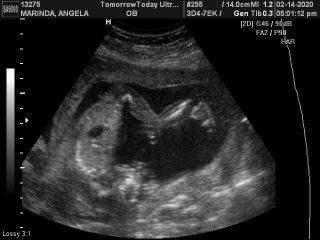

Is it normal na sumakit right side ko? I'm 20 weeks in 2 days and I cant sleep kasi sobrang sakit ng right side ko :(( helpp